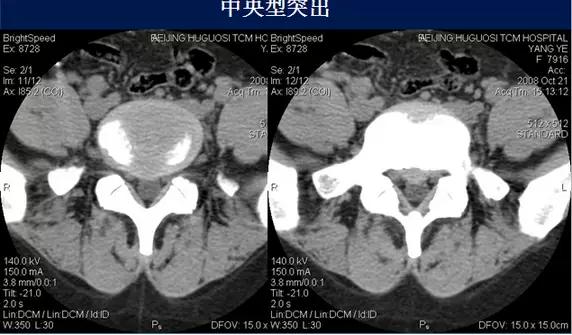

⑴中央型:椎间盘影局限性超出椎体边缘,硬膜囊可受压,硬膜外脂肪间隙变窄、消失,可伴纤维环钙化。

硬膜外脂肪间隙变窄、消失,可伴纤维环钙化。